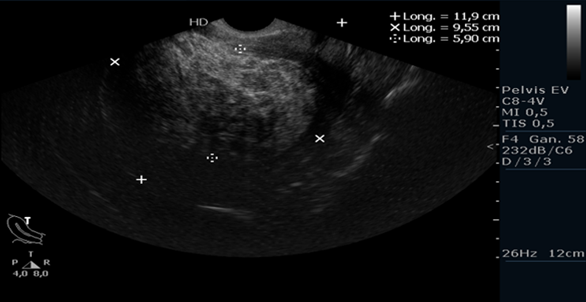

Presenta cuadro clínico de 4 años de evolución de sangrado vaginal abundante tipo menorragia, ciclos de 24 días, duración de 5 días, con volumen mayor a 80 ml (refiere cambio de toalla cada 2 horas, completamente impregnada), ocasionalmente presenta metrorragias, asociado con dolor pélvico crónico; síntomas que han alterado su calidad de vida y desempeño laboral. Fue valorada en consulta de ginecología hace 2 años, se le pide una ecografía transvaginal con diagnóstico de hiperplasia endometrial, no se realizó biopsia. Le iniciaron tratamiento con anticonceptivos orales a base de levonogestrel a dosis de 25 mcg vo /día por 6 meses, con mejoría parcial y episodio de reagudización del sangrado posterior a la suspensión del tratamiento. Se le realiza nueva ecografía transvaginal 2 años después, reportando engrosamiento endometrial de 59 mm (ver Figura 1). Se le realizó curetaje biopsia que reportó endometrio secretor, negativa para displasia o malignidad.

En nuestro caso, tenemos una paciente posmenopáusica, con sangrado uterino anormal y ecografía con grosor endometrial de 59 mm, que según la evidencia analizada en los diferentes estudios, está muy por encima del valor de corte definido como de alta sensibilidad y especificidad para el diagnóstico de carcinoma endometrial. Por lo que para esta paciente se consideró mandatorio un estudio histológico en forma prioritaria, que si bien, el resultado fue negativo para malignidad, es sin duda alguna el procedimiento más pertinente a seguir con la paciente con un adecuado soporte en la literatura.